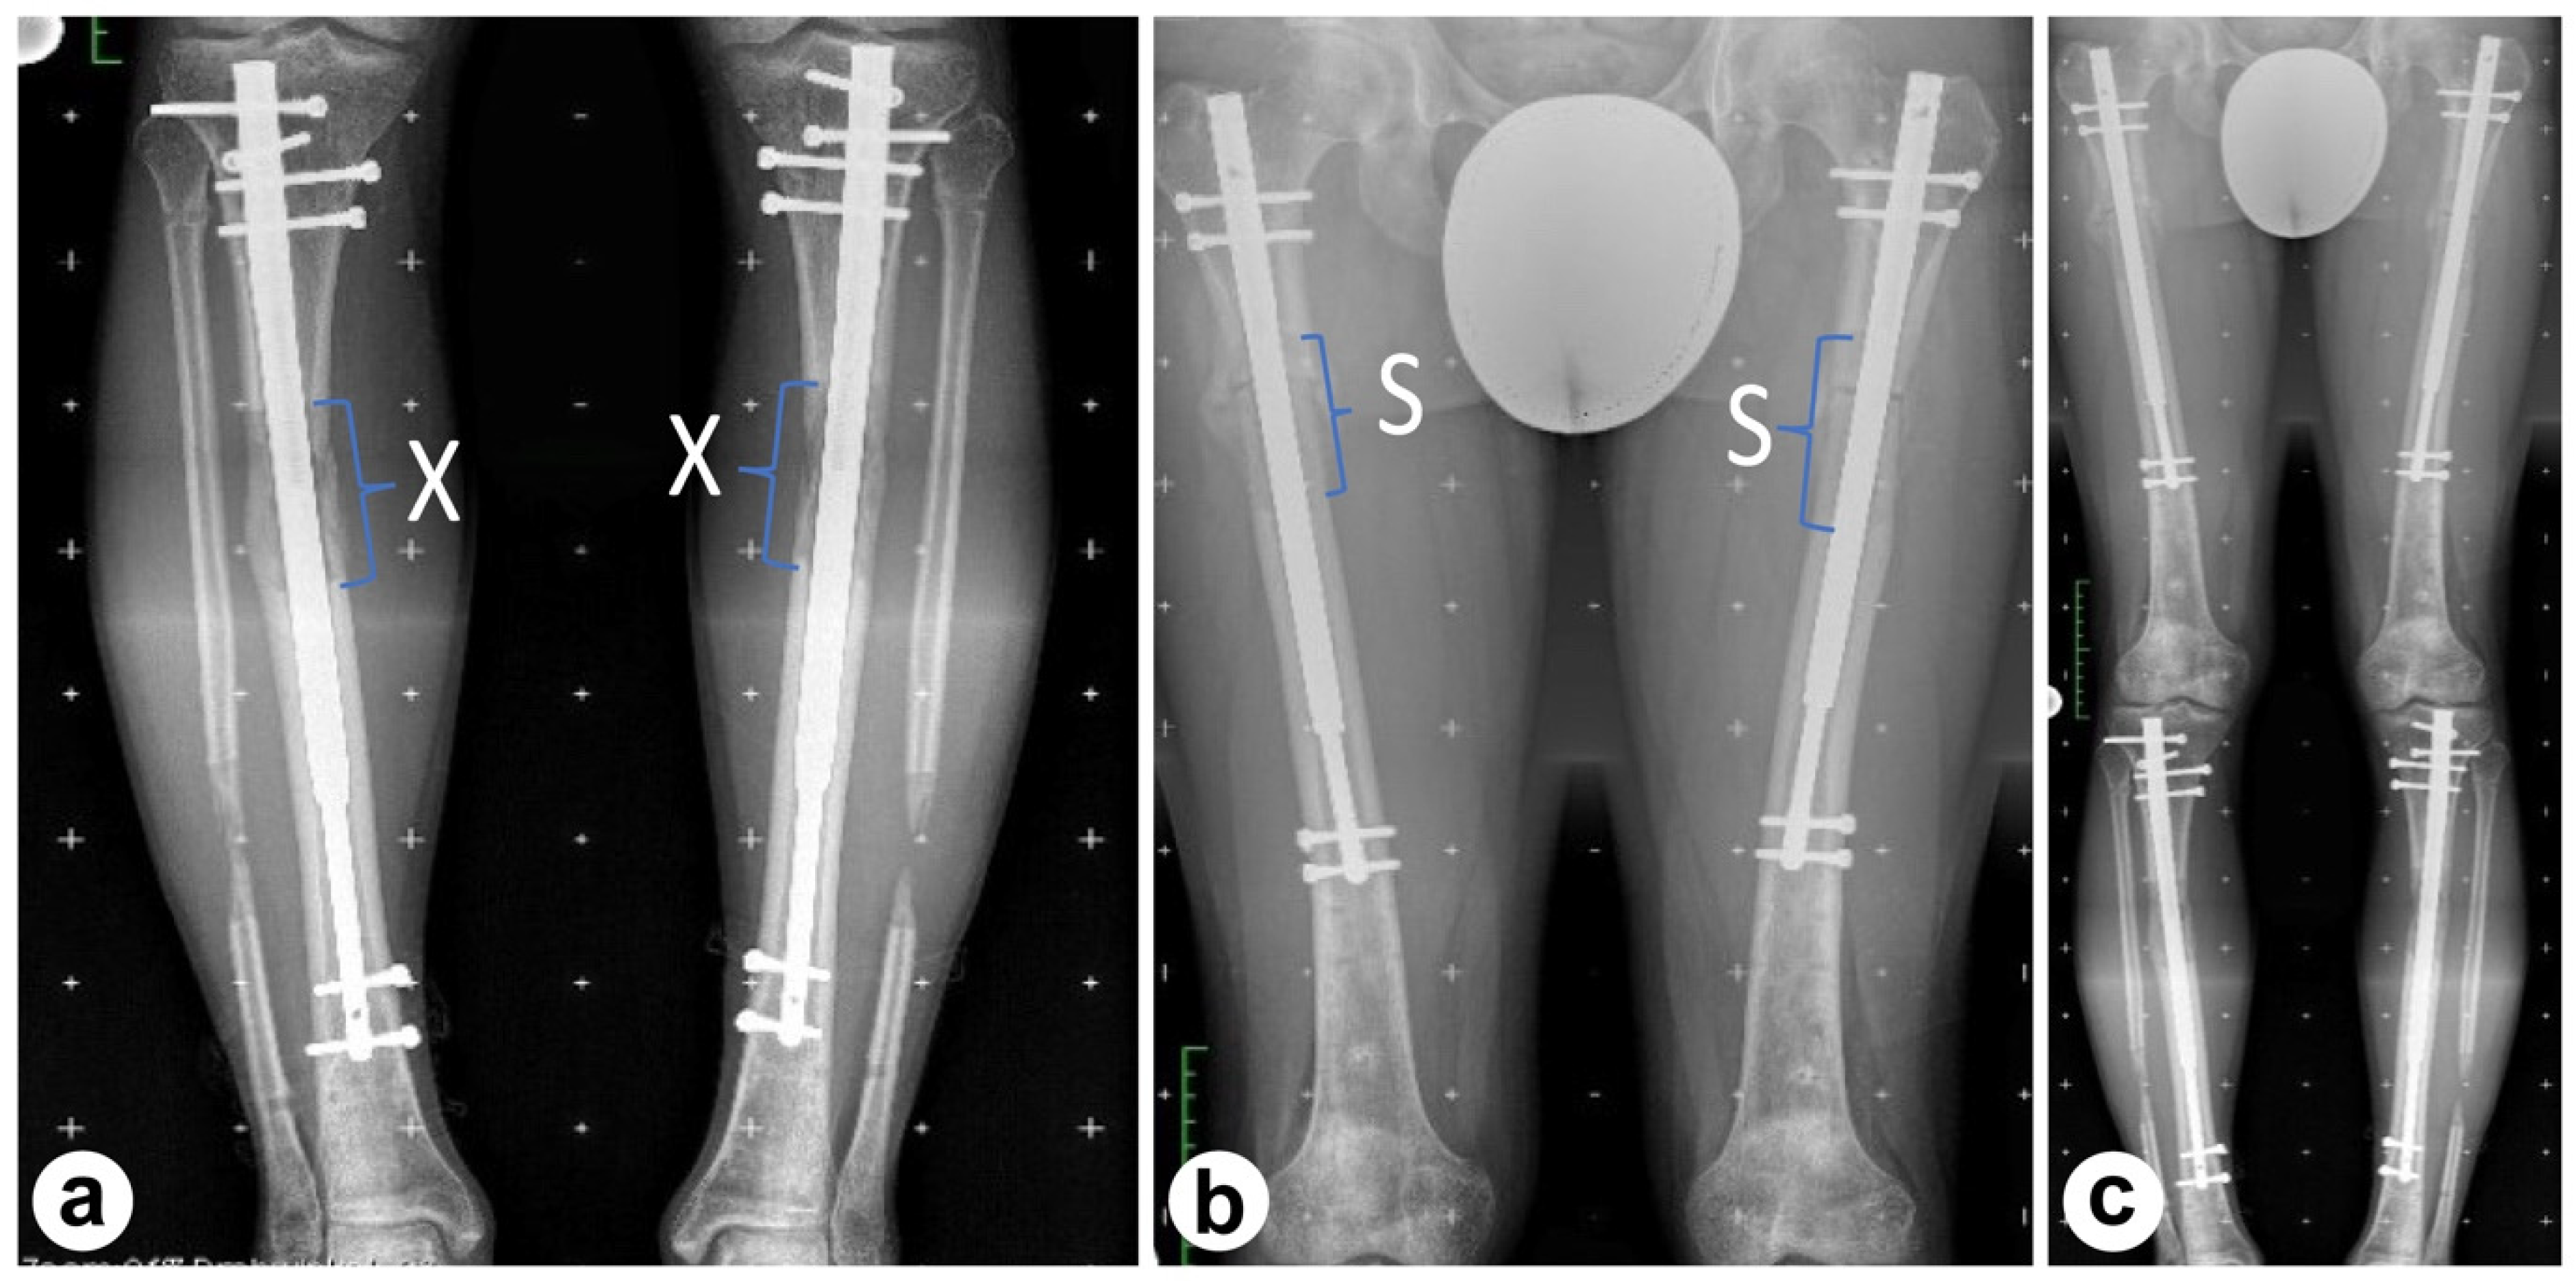

Tibial Lengthening (June 2020)

2.4. Post-Lengthening Adjustments and Femoral Shortening

Femoral Shortening (January 2021)